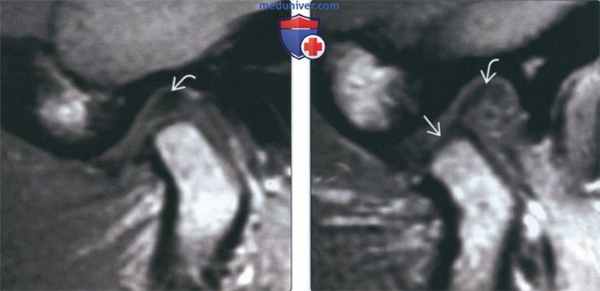

(Слева) На косой сагиттальной МРТ (Т1 ВИ) ВНЧС с закрытым ртом визуализируется задний пучок диска, находящийся в нормальном положении относительно мыщелка.

(Справа) На косой сагиттальной МРТ (Т1 ВИ) ВНЧС у этого же пациента визуализируется задний пучок диска, остающийся спаянным с самыми верхними отделами суставной ямки. Область соединения переднего пучка с переходной зоной находится между мыщелком и суставным возвышением. Отсутствует трансляция диска относительно заднего ската суставного возвышения.